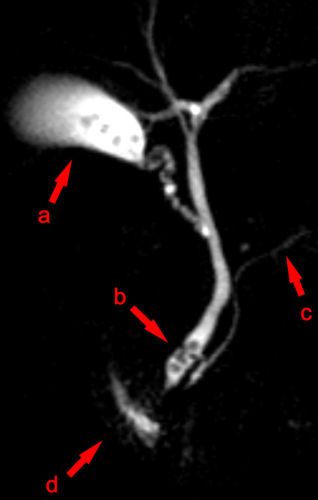

back Magnetic resonance cholangiopancreatography

Source: MRCP Choledocholithiasis.jpg